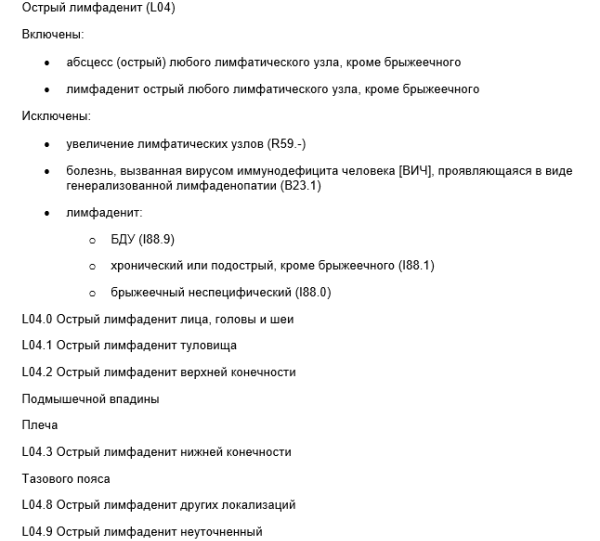

Код мкб 10 атерома головы

Код мкб 10 атерома головы 109 фото